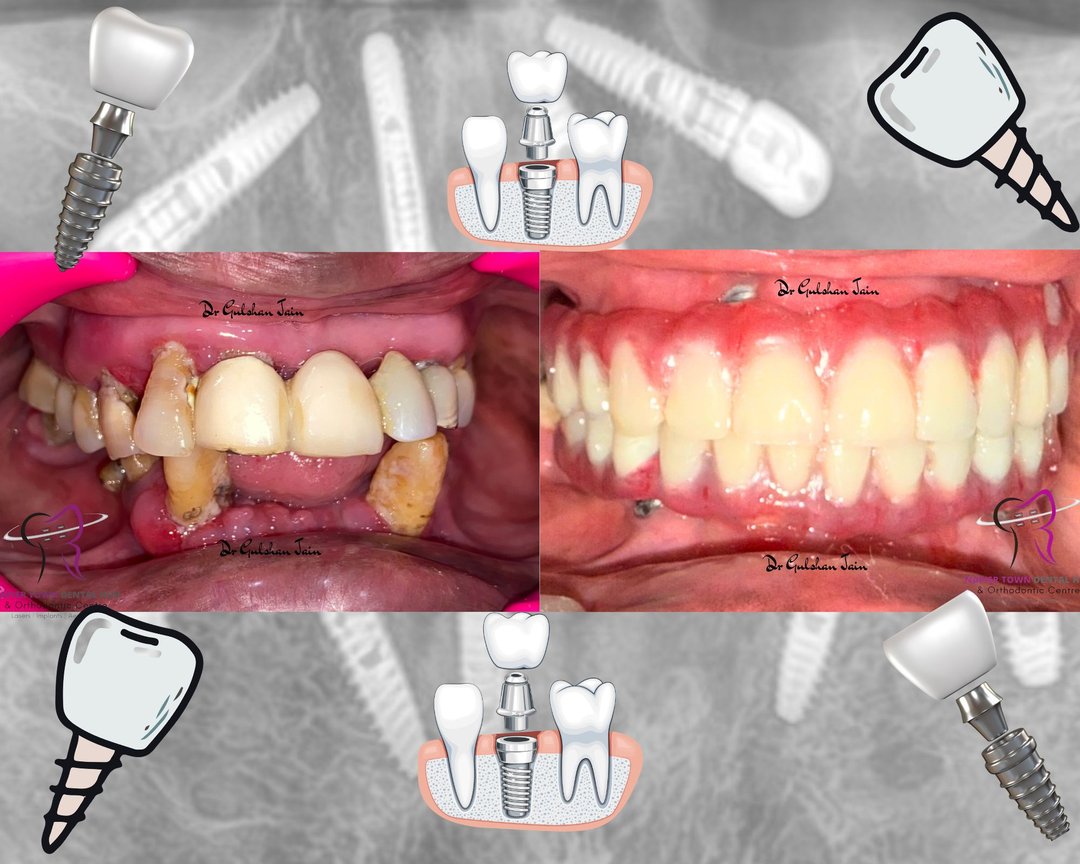

Welcome to our gallery

See how our company transforms ideas into reality. This gallery is a visual testament to our work and achievements.